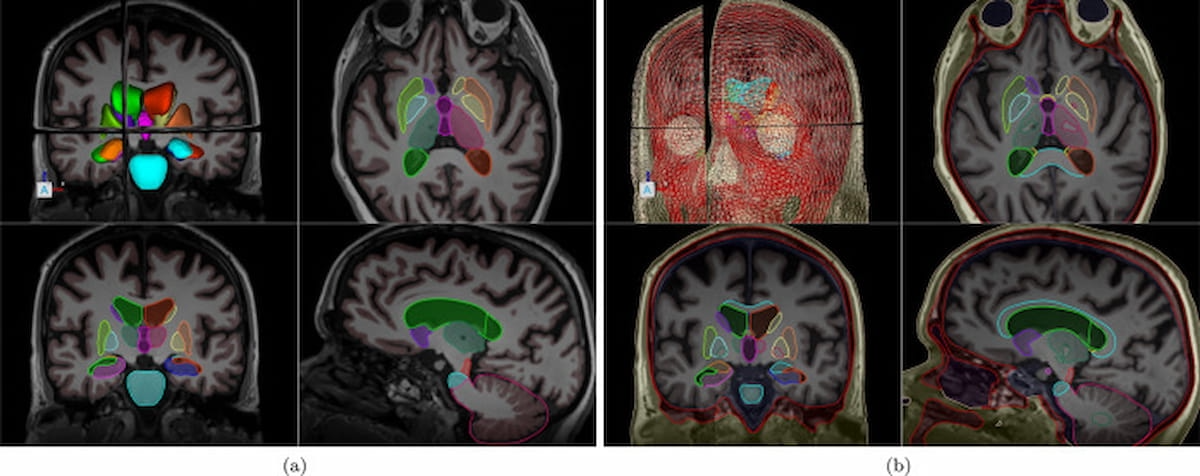

Utilizing brain MRI and cognitive assessments, the newly FDA-approved, AI-powered software platform BrainSee can reportedly predict the progression of amnestic mild cognitive impairment (aMCI) to Alzheimer’s dementia within five years.